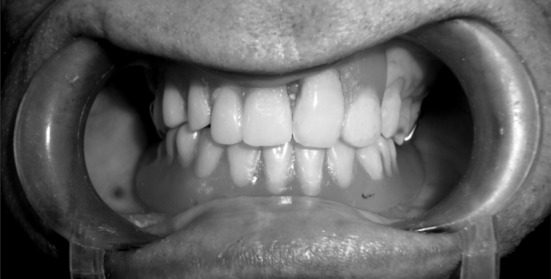

Fig. 13.

Post-operative upper partial denture and lower magnet retained overdenture